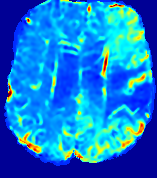

LesionRefer to captionRefer to captionRefer to captionRefer to captionRefer to captionRefer to caption𝐕rgbsubscript𝐕𝑟𝑔𝑏{\bf{V}}_{rgb}Refer to captionRefer to captionRefer to captionRefer to captionRefer to captionRefer to caption𝐕2subscriptnorm𝐕2{\|\bf{V}}\|_{2}Refer to captionRefer to captionRefer to captionRefer to captionRefer to captionRefer to captionRefer to caption3.53.53.52.82.82.82.12.12.11.41.41.40.70.70.70.00.00.0(mm/s)𝑚𝑚𝑠(mm/s)D𝐷DRefer to captionRefer to captionRefer to captionRefer to captionRefer to captionRefer to captionRefer to caption0.0200.0200.0200.0160.0160.0160.0120.0120.0120.0080.0080.0080.0040.0040.0040.0000.0000.000(mm2/s)𝑚superscript𝑚2𝑠(mm^{2}/s)Slice #1Slice #2Slice #3Slice #4Slice #5Slice #6

Figure 3: PIANO feature maps for one stroke patient, where the lesion is located in the left hemisphere. Top row: segmented stroke lesion region (white) on different slices, obtained from ISLES 2017. The corresponding slices for the PIANO feature maps are shown in the following rows.

For a better insight into an estimated velocity field 𝐕𝐕{\bf{V}} and diffusion field 𝐃𝐃{\bf{D}}, we compute the following maps: (1) 𝐕rgbsubscript𝐕𝑟𝑔𝑏{\bf{V}}_{rgb}: Color-coded orientation map of 𝐕=(Vx,Vy,Vz)T𝐕superscriptsuperscript𝑉𝑥superscript𝑉𝑦superscript𝑉𝑧𝑇{\bf{V}}=(V^{x},V^{y},V^{z})^{T}, obtained by normalizing 𝐕𝐕{\bf{V}} to unit length and mapping its 3 components to red, green, blue respectively; (2) 𝐕2subscriptnorm𝐕2\|{\bf{V}}\|_{2}: 222 norm of 𝐕𝐕{\bf{V}}; (3) D𝐷D: scalar field in Eq. 5.

Fig. 3 and Fig. 4 show the PIANO feature maps estimated from two ISLES 2017 patients: all are highly consistent with the lesion in both cases. Details of the blood flow trajectories are revealed in 𝐕rgbsubscript𝐕𝑟𝑔𝑏{\bf{V}}_{rgb} by the ridged patterns and the sharp changes of colors in the unaffected (right) hemisphere, while the flat patterns appearing within the lesion provide little directional information about the velocity and indicate low velocity magnitudes. Velocity magnitudes are more directly visualized via 𝐕2subscriptnorm𝐕2\|{\bf{V}}\|_{2}, from which one can easily locate the lesion where 𝐕2subscriptnorm𝐕2\|{\bf{V}}\|_{2} is low. D𝐷D also indicates lower diffusion values in the lesion, though with less contrast potentially due to the fact that it captures the accumulated effect of CA diffusion at the voxel-level.